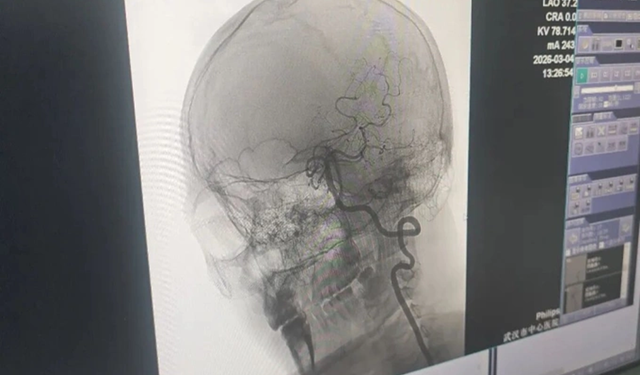

Sau khi được đưa đến bệnh viện cấp cứu, người đàn ông được chẩn đoán mắc chứng bóc tách động mạch đốt sống do áp lực không đúng cách và mạnh lên cổ, chứ không phải đột quỵ do xơ cứng động mạch thông thường. Điều này có thể gây ra nhồi máu não cấp tính, làm tắc nghẽn các mạch máu chính và có khả năng đe dọa tính mạng người bệnh nếu không được điều trị kịp thời.

Qua khai thác bệnh sử và chẩn đoán hình ảnh, bác sĩ Cảnh Bình, Trưởng khoa Thần kinh, khẳng định nguyên nhân nhồi máu não xuất phát từ vết bóc tách động mạch vùng cổ. Bà phân tích vùng cổ tập trung nhiều cấu trúc thần kinh và mạch máu quan trọng. Do nằm trong các lỗ mỏm ngang của đốt sống cổ, động mạch đốt sống có vị trí tương đối cố định. Những tác động ngoại lực sai cách như xoay, kéo giãn hoặc xoa bóp quá mạnh rất dễ xé rách lớp nội mạc mạch máu, tạo thành túi bóc tách và sinh ra huyết khối.